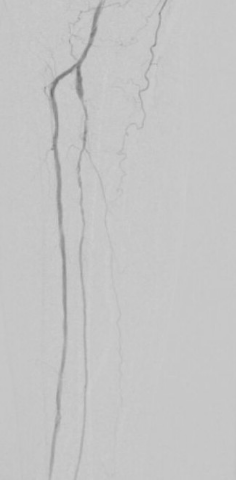

7. 术后造影血流恢复

本例患者股浅动脉重度闭塞,股浅远端重度钙化病变近收肌管,利用Shockwave冲击波球囊获得满意的管腔准备后联合使用DES,为保障远期通畅植入支架,支架膨胀形态理想。